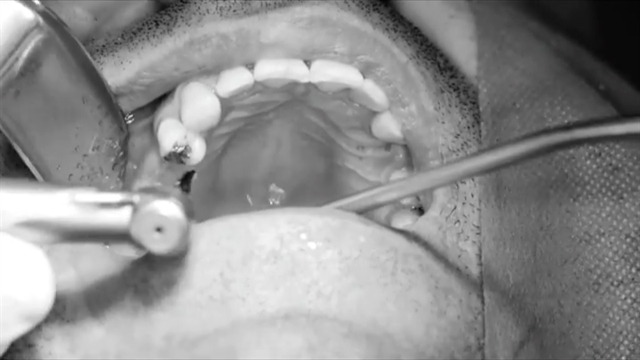

پخش صدا دکتر وحید دهقان: کاشت ایمپلنت اشتراکگذاری لیست پخش ۰ نظر ۰ نظر گزارش تخلف بیشتر گزینههای بیشتر لیست پخش لایکها گزارش تخلف ۰ لایک مرکز ایمپلنت دکتر دهقان منتشر شده در تاریخ ۱۴۰۰/۱۱/۰۸ این کانال دنبال شد دنبال کردهاید دنبال کردن این کانال دنبال کردن وب سایت دکتر وحید دهقانwww.drdehghanclinic.com ادامه آموزش نظرات لبخند لبخند لغو ثبت نظری برای نمایش وجود ندارد.